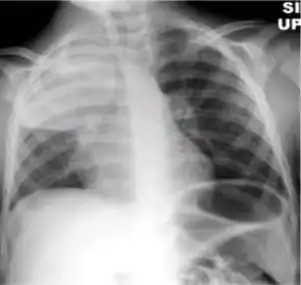

Chest X-ray

Tuberculosis creates cavities visible in x-rays like this one in the patient's right upper lobe.

A posterior-anterior (PA) chest X-ray is the standard view used; other views (lateral or lordotic) or CT scans may be necessary.

In active pulmonary TB, infiltrates or consolidations and/or cavities are often seen in the upper lungs with or without mediastinal or hilar lymphadenopathy.[1] However, lesions may appear anywhere in the lungs. In HIV and other immunosuppressed persons, any abnormality may indicate TB or the chest X-ray may even appear entirely normal.[1]